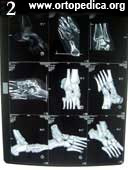

Пример №11 Подтаранный артродез при вальгусной деформации и артрозе подтаранного сустава

1. Рентгенография стопы - артроз подтаранного сустава

2. Спиральная компьютерная томография стопы - плосковальгусная деформация

3. Рентгенограмма в боковой проекции после операции подтаранного артродеза

4. Рентгенограмма после операции подтаранного артродеза

5. Рентгенограмма через 2 месяца после операции подтаранного артродеза